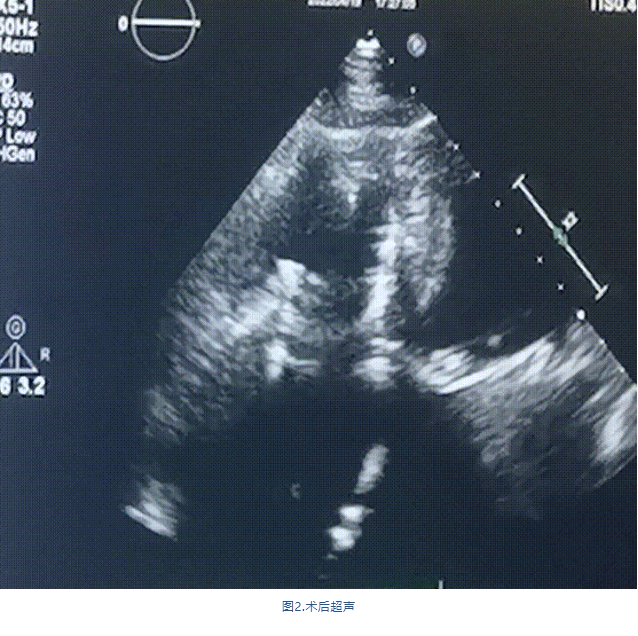

此次手術(shù)在全麻下進(jìn)行,采用經(jīng)右側(cè)頸靜脈入路。術(shù)中在經(jīng)食道超聲和DSA的指引下多個(gè)維度精細(xì)調(diào)整輸送器角度,在達(dá)到正確位置后,逐步釋放瓣膜錨定裝置和盤(pán)片,最終完成瓣膜植入。術(shù)后患者右房壓明顯下降,術(shù)后超聲提示人工三尖瓣同軸性良好,瓣架固定牢靠,無(wú)反流和瓣周漏,血壓術(shù)后即刻上升20mmHg左右,手術(shù)后監(jiān)護(hù)室順利拔除氣管插管,3天后恢復(fù)良好,予以出院。